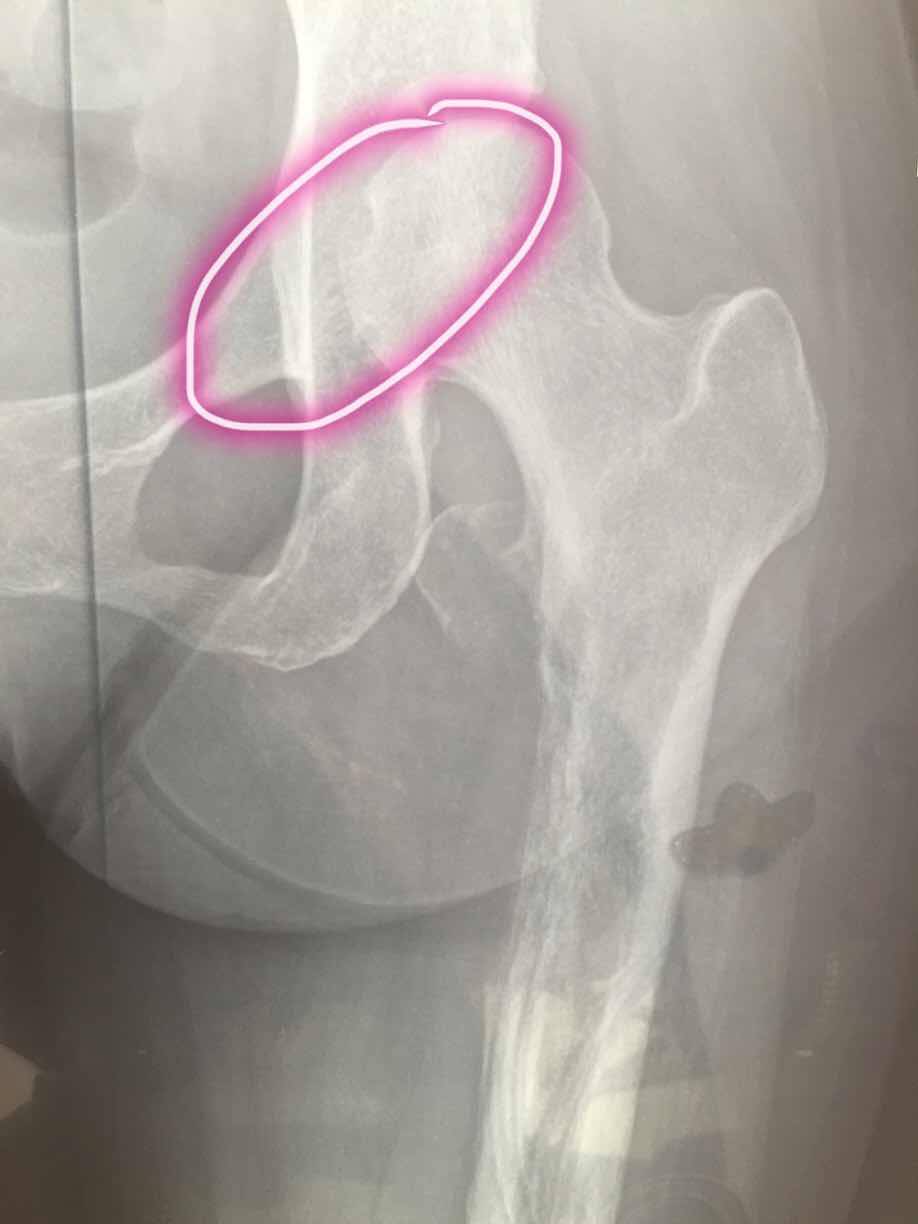

这是第一次确诊是拍的腿部ct,因为是腿疼才去检查,直接去的骨科医院,没想到确是转移,主要是左大腿疼痛,在家以为是腰间盘卧床躺了3月,期间就第三个月疼痛无比,刚开始两月还好,也能行走,就是腿疼,尽量不走,等再去医院检查的当天还把左大腿根掰了下,可能造成了骨裂,图片为最后一张图画圈的那里,打了两次骨转针。吃了一个月易瑞沙,腿已经不疼了,但是由于骨裂那块,还是卧床不让行走,医生也说让静养,怕骨折。我想问问大家有没有这方面的,我家这个情况该怎么办。还有机会在站起来行走吗,目前左腿肌肉萎缩的还比较厉害,拜托大家。

是股骨头处骨裂?